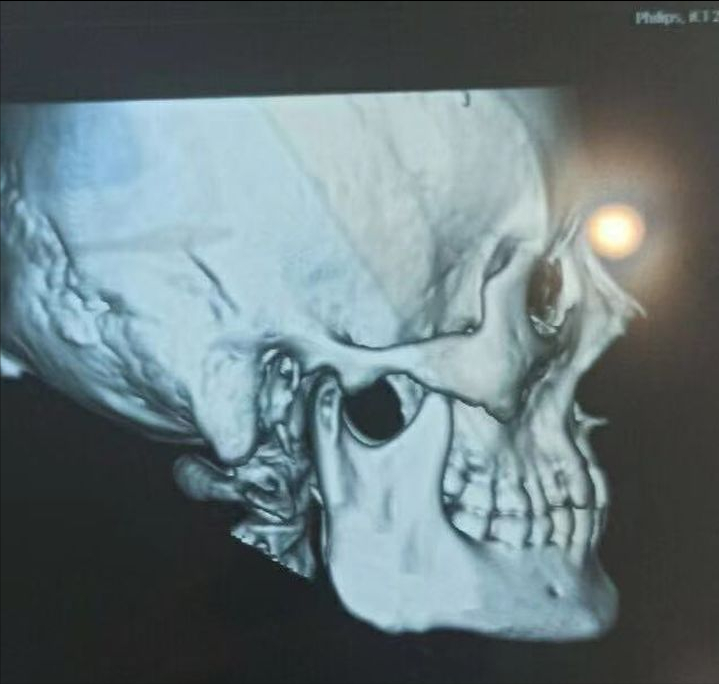

就像这种下颌角,术前是可以看出来有些宽大的。

术后的果留下二次角。

这种是医生的技术不行,可以看出来,是做了留角的,如果角度处理在一点会则会更一点,不要看到网上做的留角的失败了,就觉得不能做留角。

这种骨头类的二次修复,也是的不好做的,一般的医生都做不好,可操作的空间比较小,怕切到神经线。

一刀切的下颌角就会造成二次角,做出来的轮廓就不好看!

图片源自网上:下颌角手术

图片源自医院:下颌角术后20天

图片源自网络:下颌角术后70天